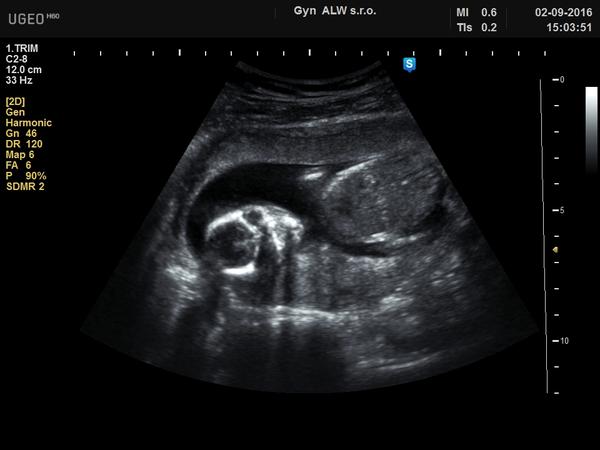

@ddaniela123 Já bych se asi taky přikláněla k holčičce. Ukážu ti ultrazvuk mého nejstaršího a mé nejmladší, je to z 19.tt, takže podobně jako ty, tak třeba ti to pomůže 😀 😉

@zoditka Tak u Tebe ta holcibja byla jasna🙂)). Me tam mate u te moji fotky ten vyrustek, co vypada jako pindik🙂))doma mam 16 leteho syna, tak bych si prala holcinku. Jinak moc dekuji

@alexis01 pindik jak vysitej 😉